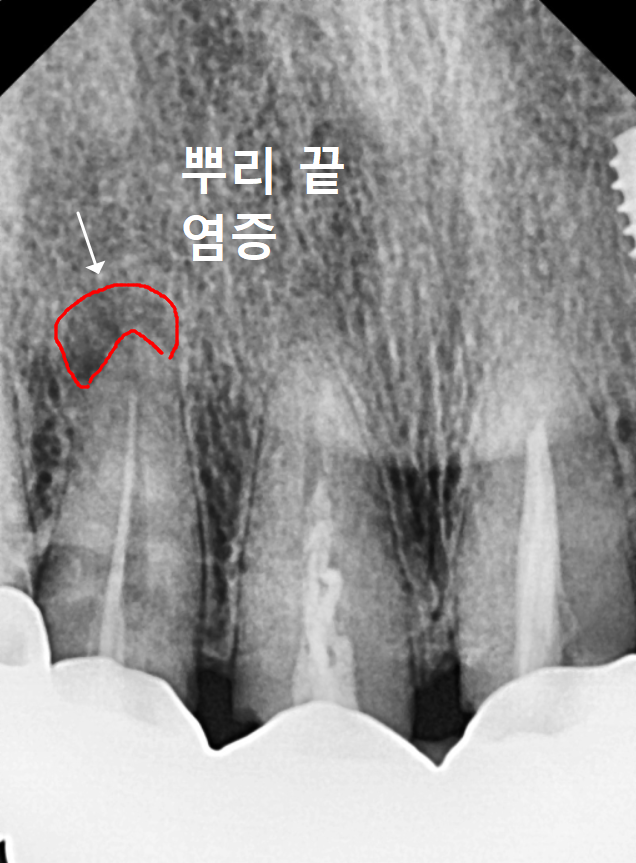

CT 상으로 확인한 오른쪽 위 송곳니(#13)는

뿌리 끝 염증으로 잇몸뼈까지 녹아있었죠.